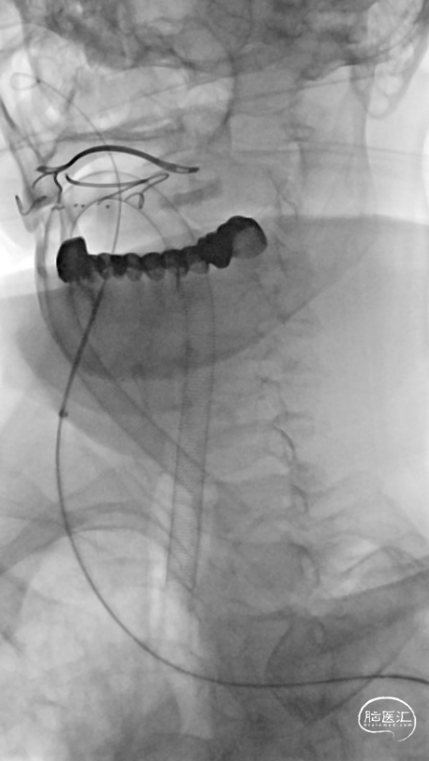

复查造影见支架展开良好,支架内及远端血流通畅,TICI分级3级。术顺,术毕,Proglide缝合术口。

术后第一天复查颅脑CT未见异常染色及大面低密度病灶。

Trevo XP ProVue 4×20mm取栓支架全程显影,能准确定位闭塞段血管,并在取栓过程通过支架形态变换间接推断局部是否狭窄病变,同时亦具有良好的血栓抓捕能力。Catalyst7中间导管跟踪到位性好,多次操作耐用,口径比Catalyst6大,更适合反复抽吸操作。